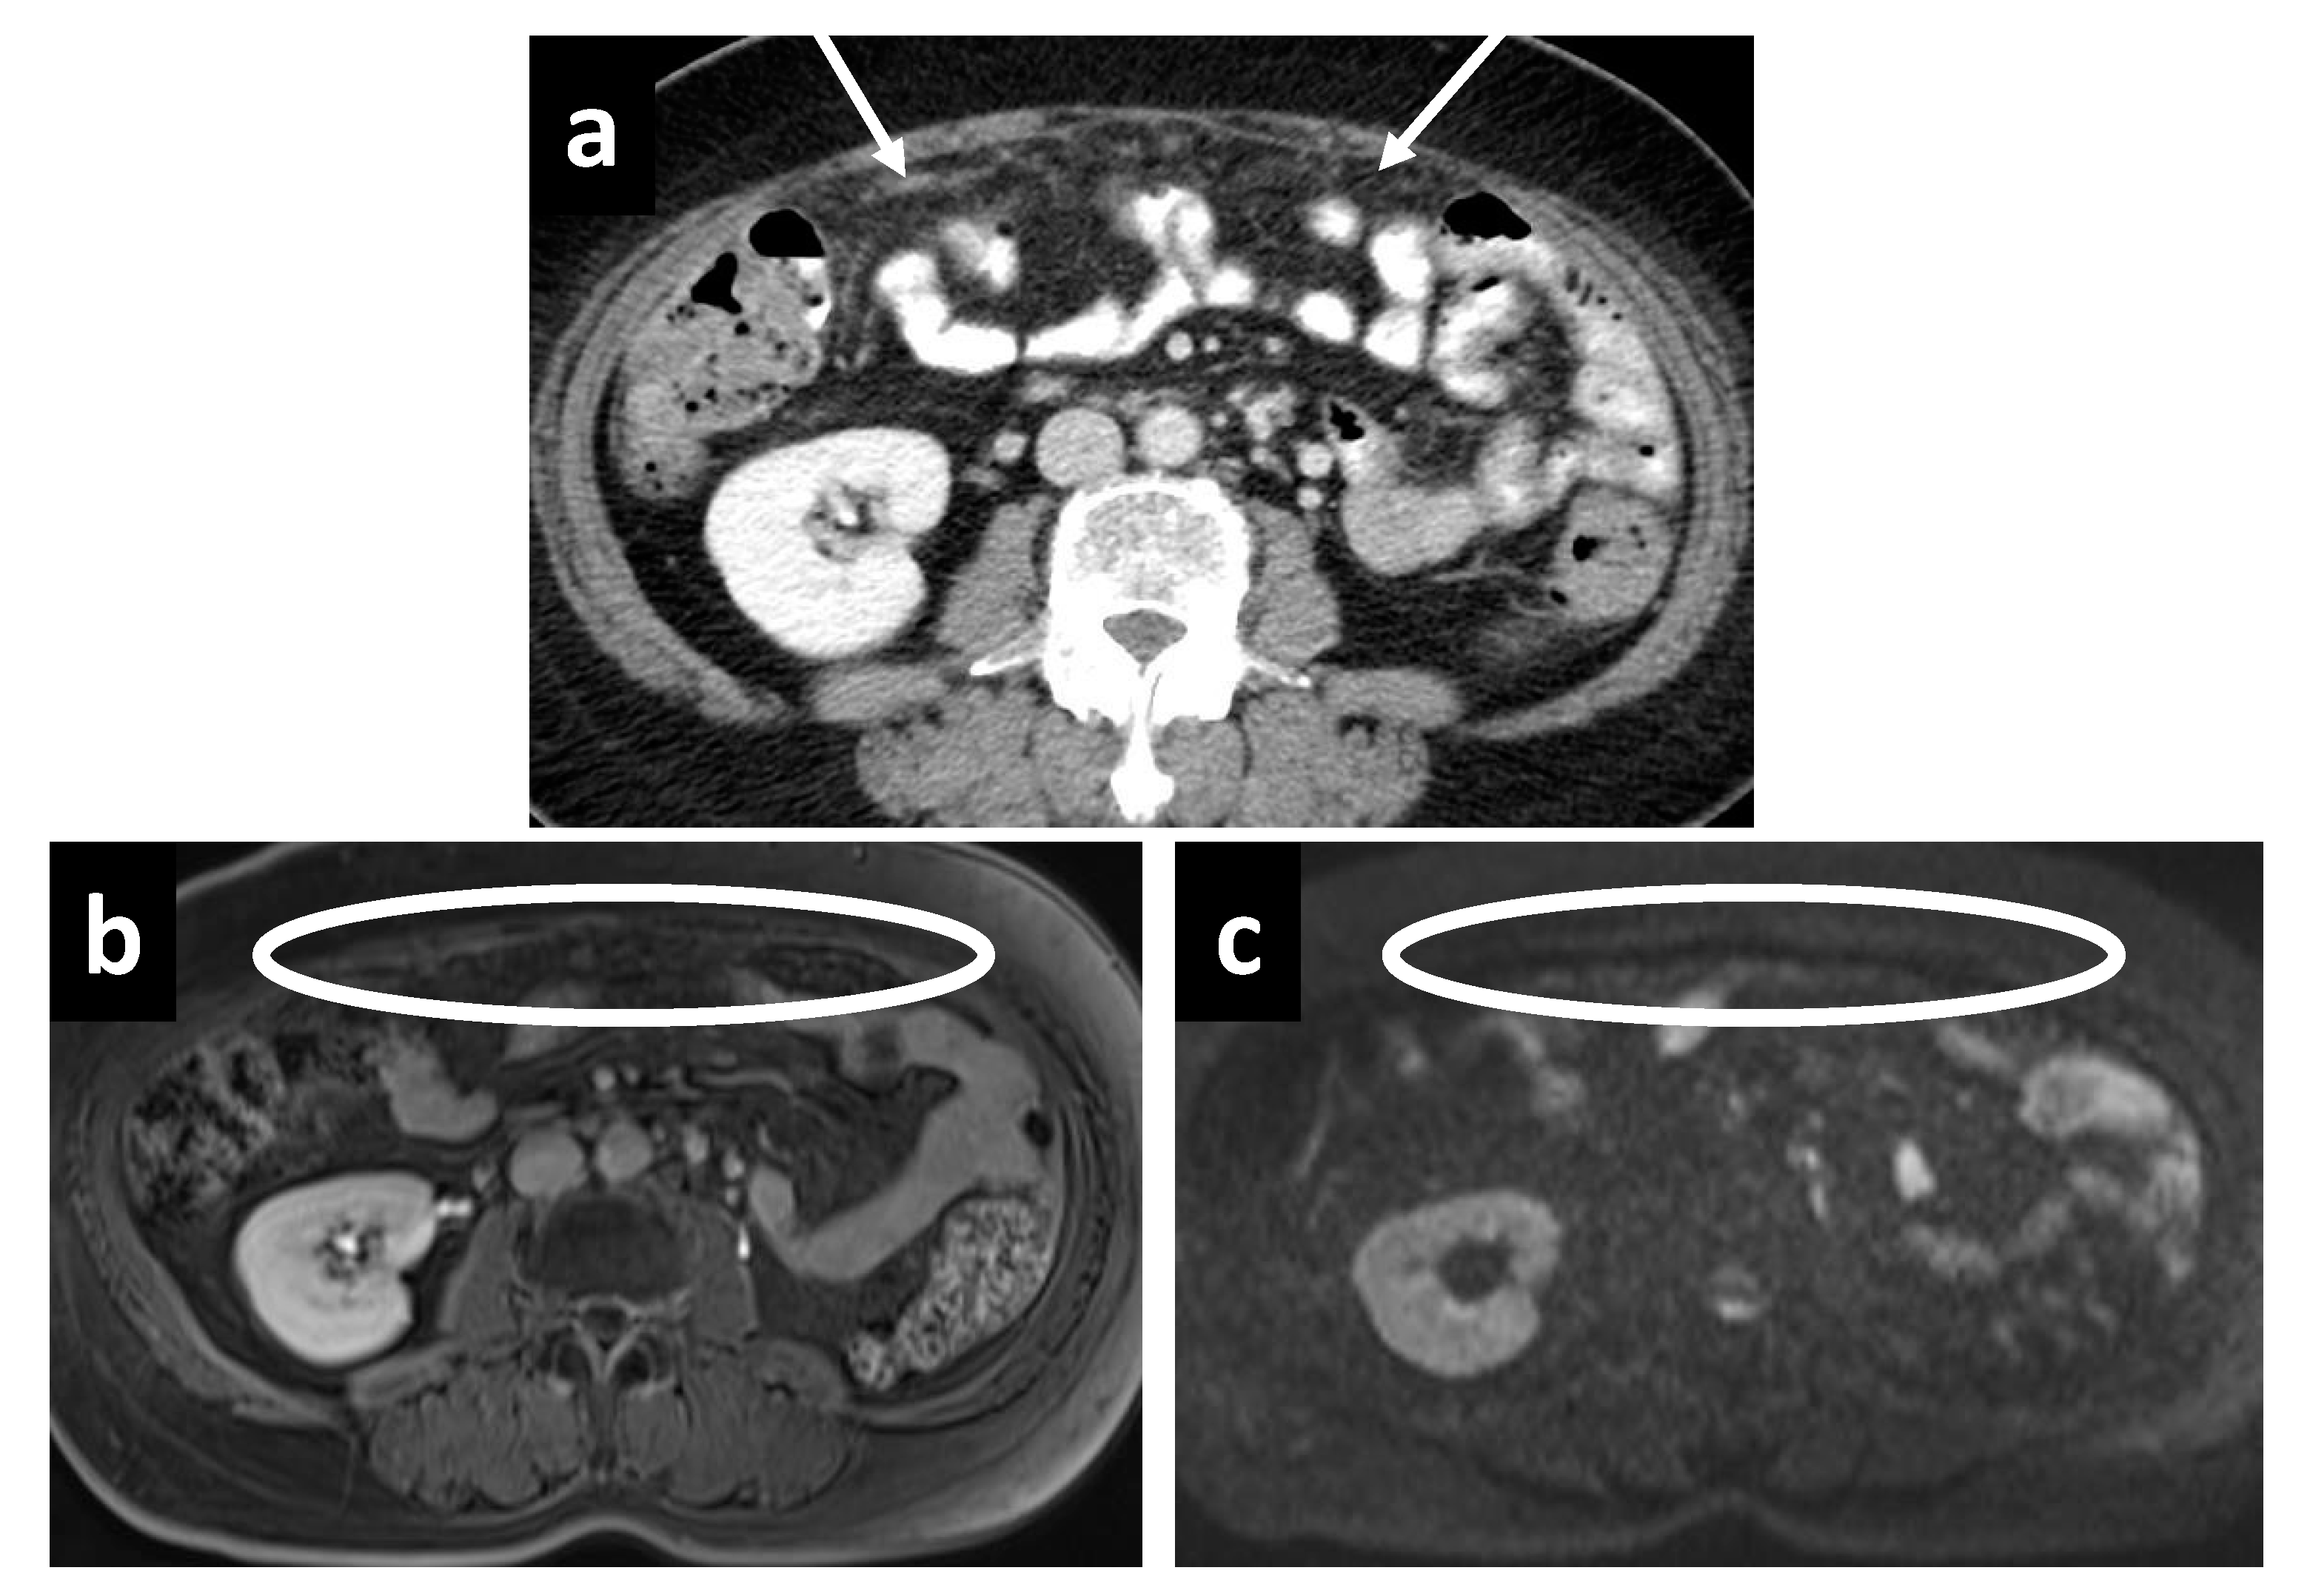

Figure 7.

A 44-year-old male with recurrent mucinous appendiceal tumor; the hypodense fluid is not well seen on the (a) CT at Morrison’s pouch but easily seen on the (b) T2W MRI, where the fluid also appears to be loculated, suggestive of a tumor deposit as opposed to bland ascites. Similarly, the pocket of fluid among small bowel loops is not as well appreciated on (c) CT but is well seen on (d) T2W MRI.